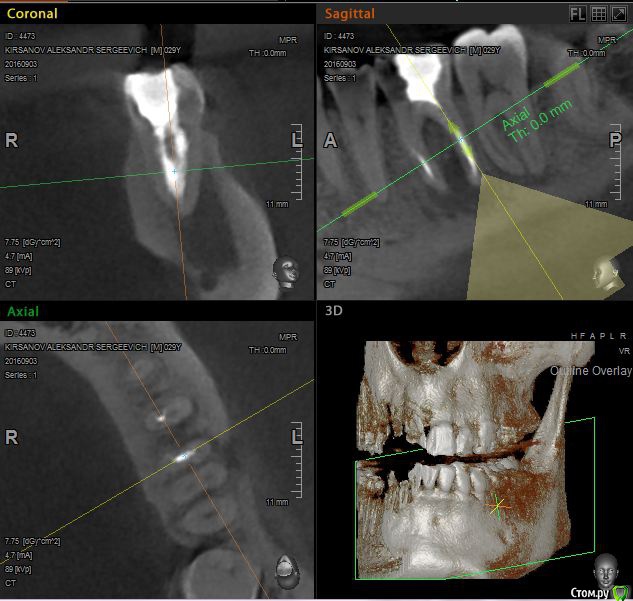

St. Опубликовано 12 ноября, 2016 Поделиться Опубликовано 12 ноября, 2016 Выложу скрины приложенного КТ. Так ответов будет больше. Есть пропущенный канал в 6 зубе. И нужно проверить на жизнеспособность соседний 7. Я бы рекомендовала попробвать перелечить и понаблюдать. Но Вы должны для себя понимать что перелечивание каналов очень сложная, дорогая и непрогнозируемая процедура. Хотя вероятность успеха достаточно высока. Если хотите гарантий - тогда удаление и имплант как восстановится кость. Еще хорошо бы знать как давно лечили каналы в этом зубе, как он вел себя после лечения, беспокоит ли сейчас? 2 Ссылка на комментарий

St. Опубликовано 12 ноября, 2016 Поделиться Опубликовано 12 ноября, 2016 11, 21 по кт без особенностей. Так что артефакты скорее всего. В 23( левый клык) есть тоже воспаление на корне. Нужно планово перелечиавать. Ссылка на комментарий